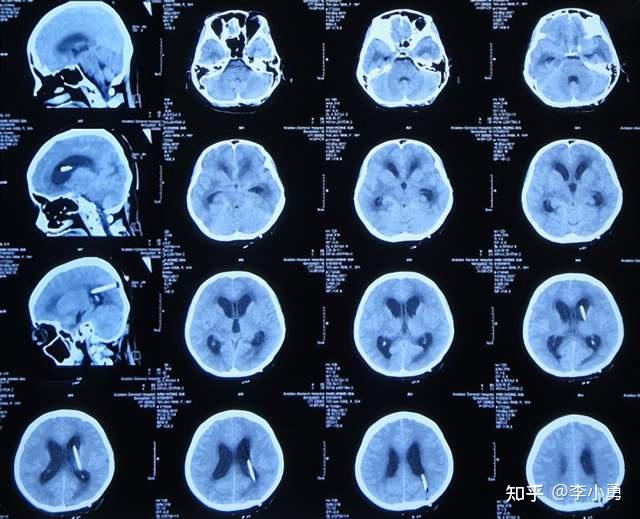

近致命性结核脑膜炎性脑积水发病后2个月内先后经4家医院治后仍无改善